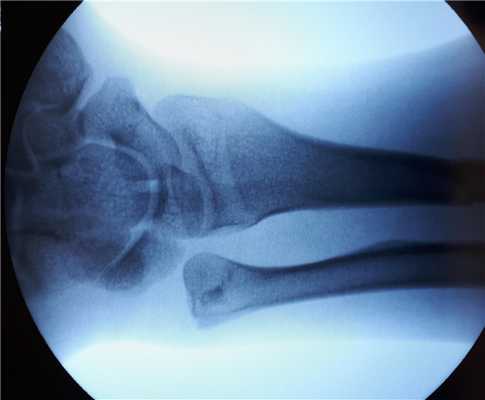

Внешний вид конечности после снятия гипсовой повязки. Рентгенограммы выполненные при помощи ЭОП на операционном столе выявили полное смещение всего дистального метафиза лучевой кости к тылу на целый поперечник.

Когда имеешь дело с таким переломом на фоне остеопороза становится ясно, что в метафизарной зоне будет «каша» из множества мелких отломков, и что суставная поверхность будет расколота минимум на 3 части.

Интраоперационно под контролем ЭОП произведена закрытая репозиция перелома.

После репозиции на рентгенограммах отчётливо виден многоооскольчатый, нестабильный характер перелома.